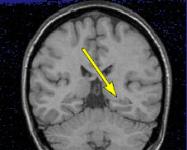

MRI FINDINGS: MRI detects mesial temporal sclerosis by demonstrating size asymmetry and abnormal signal within the atrophied hippocampus. Thin-section, high-resolution oblique coronal MR images are best for detecting these abnormalities, which can be subtle. Heavily T1-weighted images (Fig. 1) are best for detecting size asymmetry of the hippocampal gyri, while T2-weighted images (Fig. 3) and particularly FLAIR (fluid attenuated inversion recovery) images are most sensitive for detecting signal abnormalities (Fig. 2). The above images demonstrate left hippocampal atrophy and mesial temporal sclerosis (arrows).